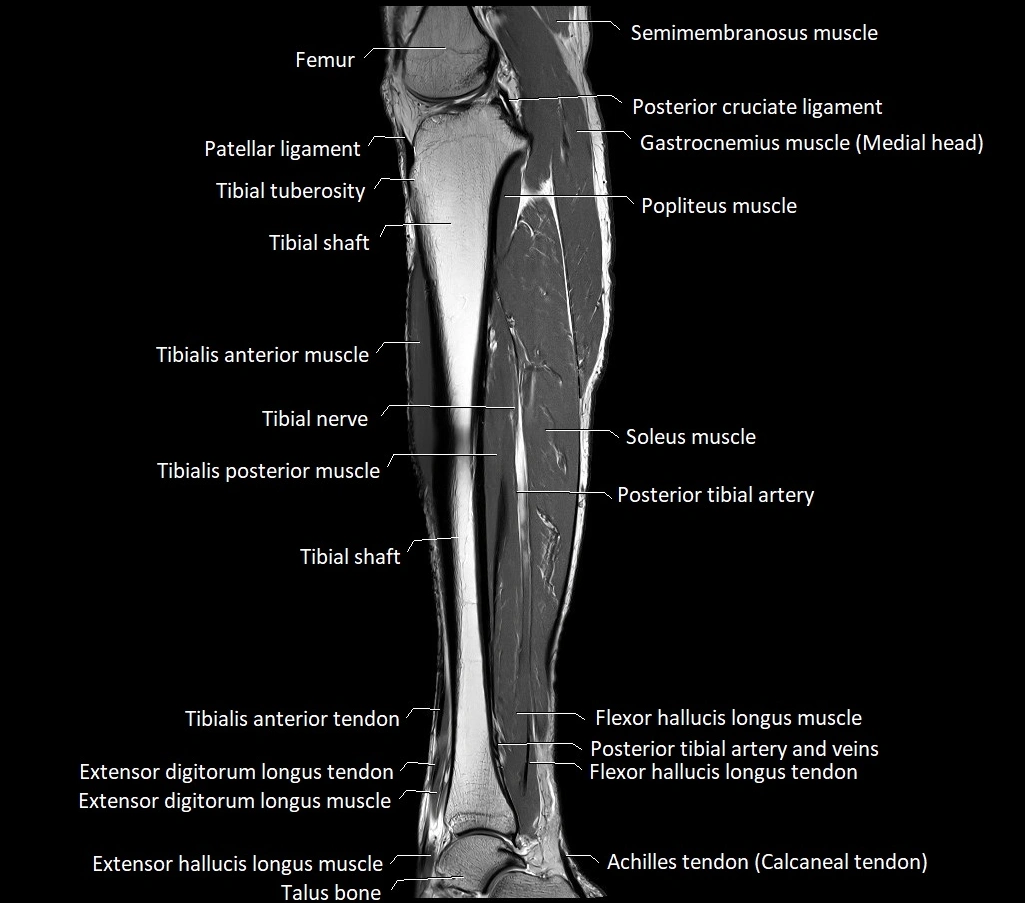

- Tibialis anterior muscle

- Tibialis anterior tendon

- Tibialis posterior muscle

- Flexor hallucis longus muscle

- Flexor hallucis longus tendon

- Extensor hallucis longus muscle

- Extensor digitorum longus tendon

- Soleus muscle

- Posterior tibial artery

- Popliteus muscle

- Posterior cruciate ligament

- Tibial tuberosity

- Patellar tendon (patellar ligament)

- Tibial nerve